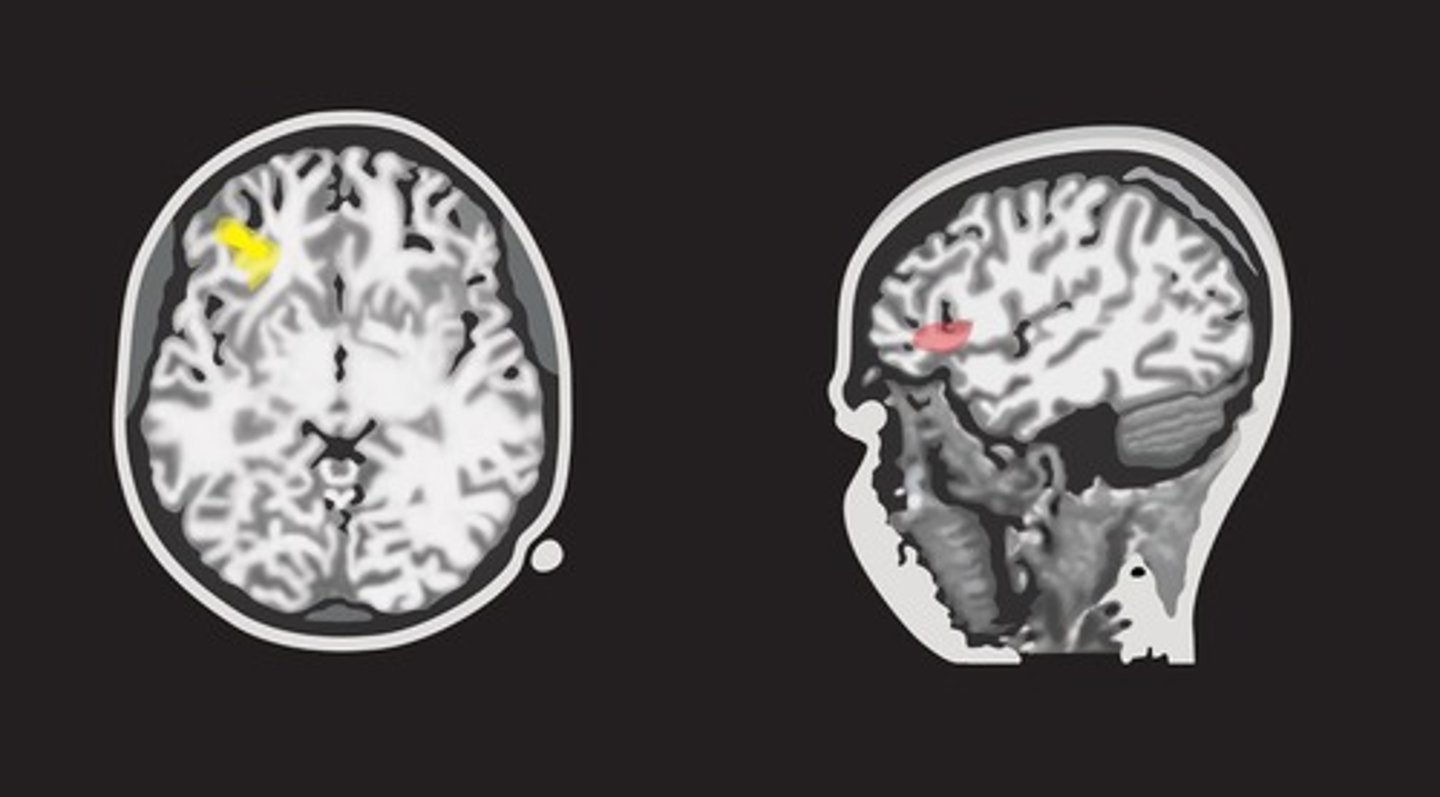

What biological factors influence the development of Theory of Mind?

Activity in the prefrontal cortex, temporal, and parietal lobes.